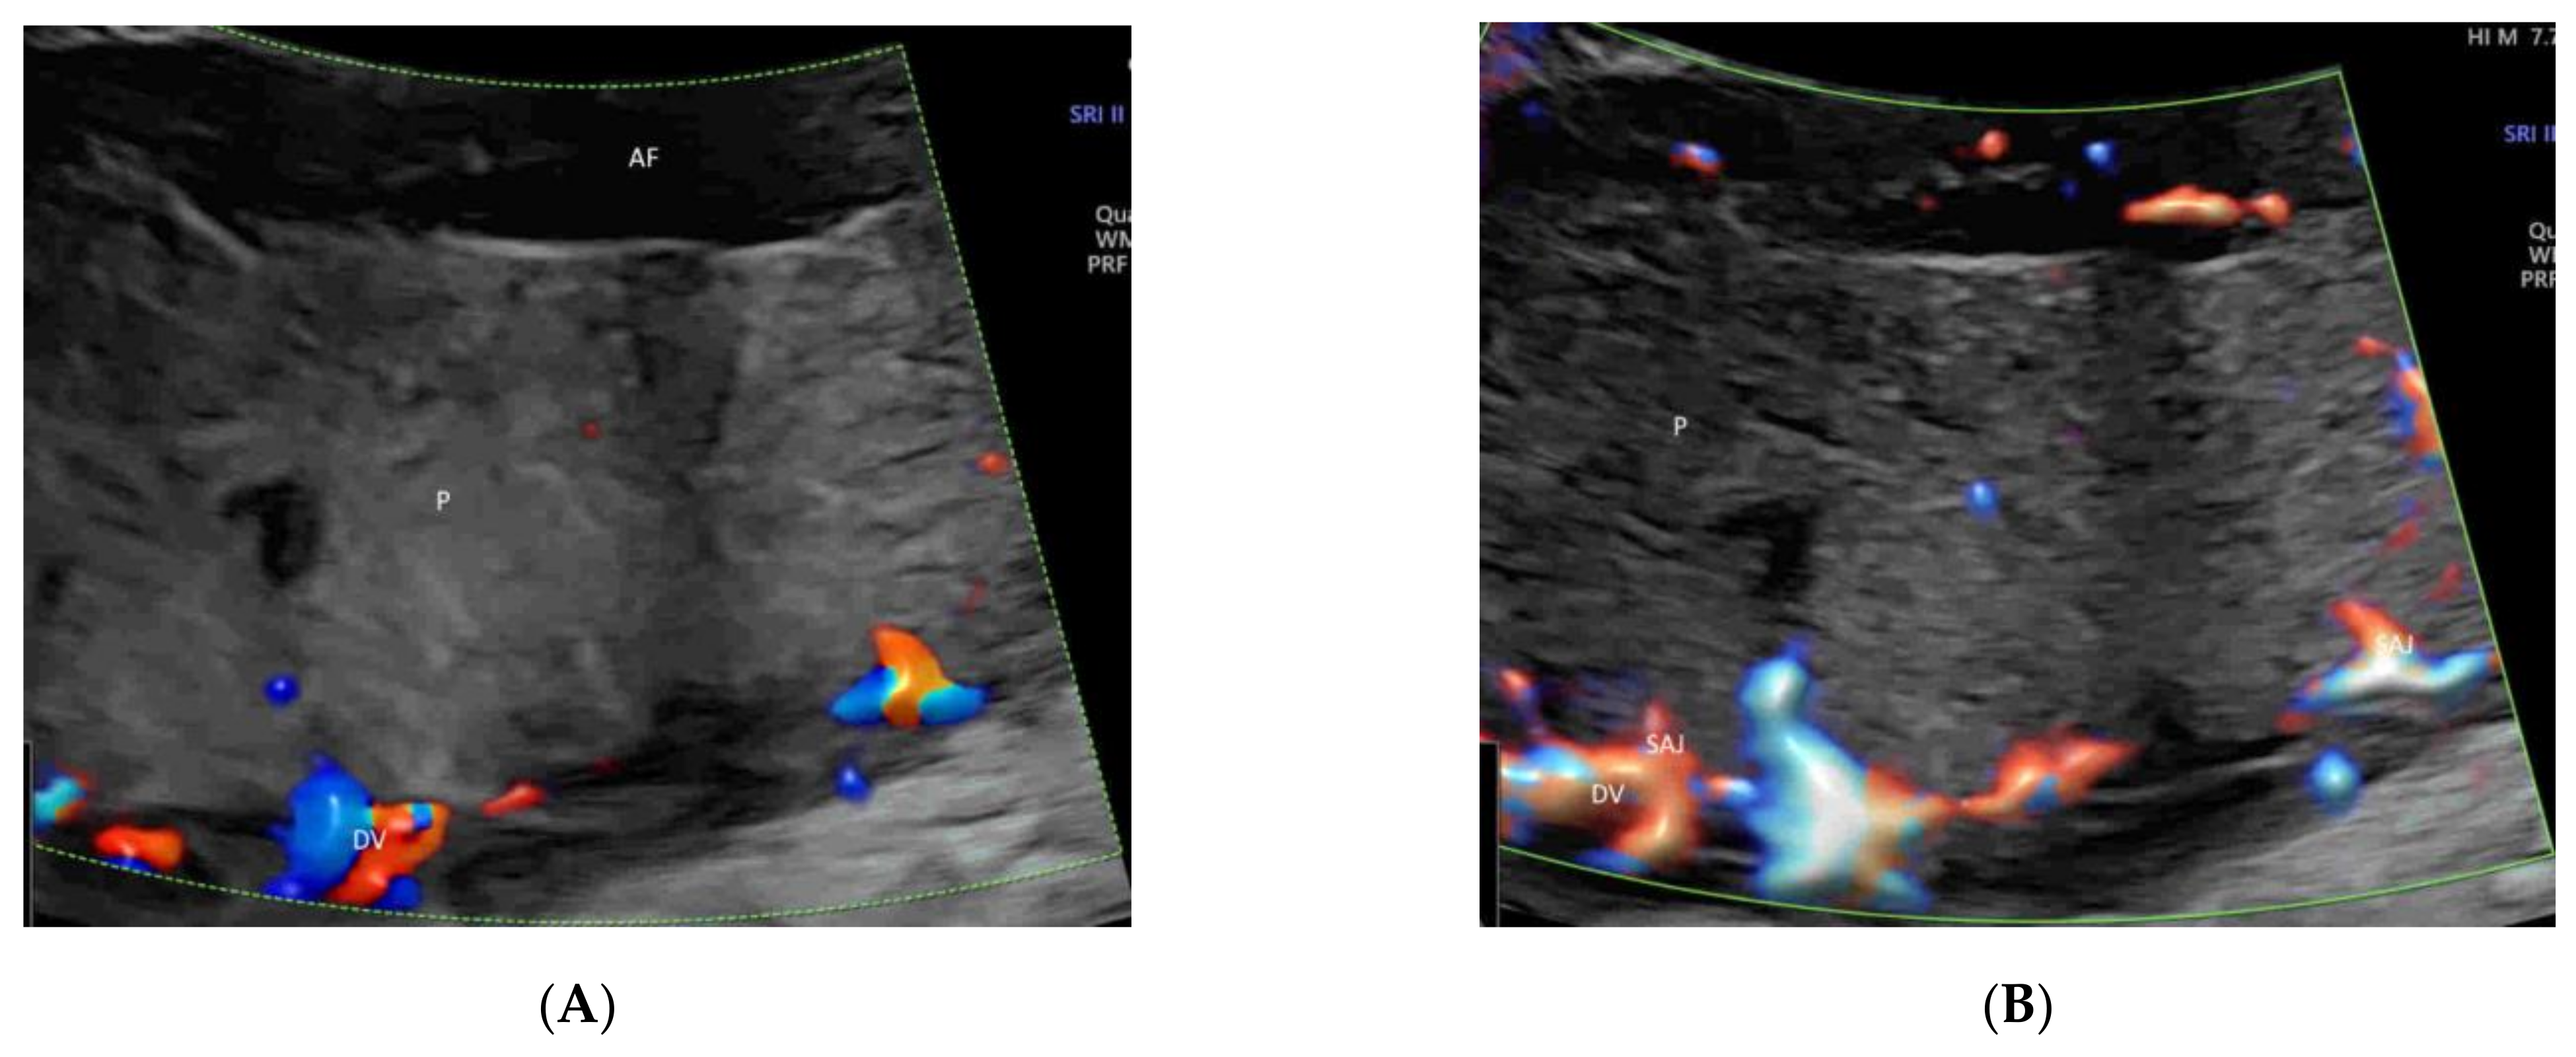

4.5. Umbilical Cord

- Leung, K.Y. Imaging of fetal precordial venous system by four-dimensional ultrasound with spatiotemporal image correlation technology. J. Clin. Ultrasound 2021. [Google Scholar] [CrossRef]